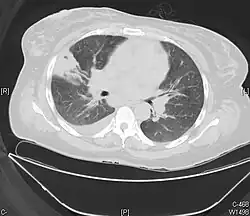

![]() Zawał prawego płuca widoczny na obrazie TK | |

Zawał płuca – martwica tkanki płucnej spowodowana przez zatrzymanie przepływu krwi przez naczynia płucne[1][2].

Zawał płuca może być pojedynczy lub mnogi (najczęściej zajmujący jedno płuco), występuje głównie w dolnych płatach, zazwyczaj styka się z opłucną[5]. Objawia się on bólem w klatce piersiowej o pochodzeniu opłucnowym[4][9], gorączką, kaszlem, dusznością, krwiopluciem[10] oraz wstrząsem[2][11][12]. W zawałach obejmujących duży obszar może pojawić się jama[8]. Inne powikłania obejmują krwotok pęcherzykowy i wysięk opłucnowy. Chorobę należy różnicować głównie z zapaleniem płuc[13] oraz nowotworem[5]; wymaga ona szybkiego rozpoznania[14][15].